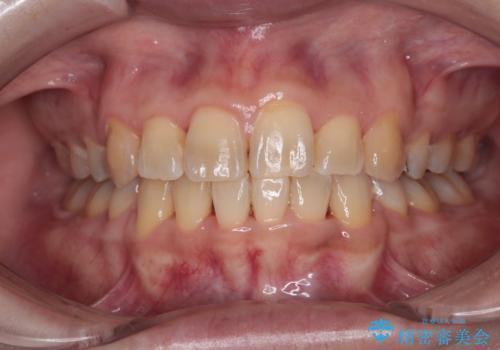

後戻りにリカバリーに少し時間を要しましたが、1年強の期間で無事に治療を終えることができました。